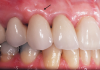

A patient presented with two defective 3-unit fixed partial dentures spanning teeth Nos. 6 through 8 and teeth Nos. 9 through 11 (Figure 7). The defective fixed partial dentures were removed (Figure 8), an impression was made, and traditional provisional fixed partial dentures without ovate pontics were placed. After the impression was sent to the laboratory, the lab technician prepared ovate pontic sites on the stone cast (Figure 9) and fabricated the new definitive bridges. On the day of insertion, the provisional fixed partial dentures were removed (Figure 10), ovate pontic sites were prepared using a teardrop-shaped diamond bur (Figure 11), and the sites were sounded to confirm that there was at least 2 mm from the base of the pontic site to the alveolar bone (Figure 12). The fixed partial dentures were cemented, and the postoperative healing was uneventful (Figure 13).

(13.) Close-up retracted 2-month postoperative view of the final fixed partial dentures spanning teeth Nos. 6 through 8 and teeth Nos. 9 through 11, along with replacement crowns for the other restored maxillary teeth.

Figure 13